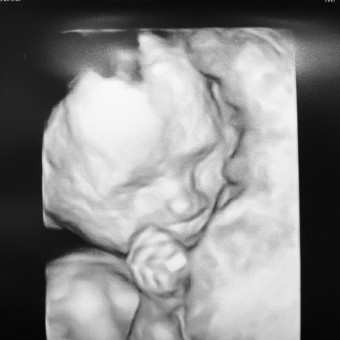

Baby Maya

Catherine LeComte-Lecce

March 30, 2026